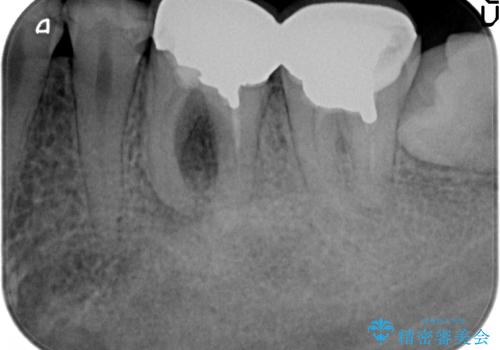

- 右下奥歯の歯茎がよく腫れるので診て欲しいといらっしゃった方の症例です。

診査の結果、右下6番目の根尖病変を認めたため再根管治療を行いました。

また右下7も根管充填が不十分なため再根管治療を行いました。